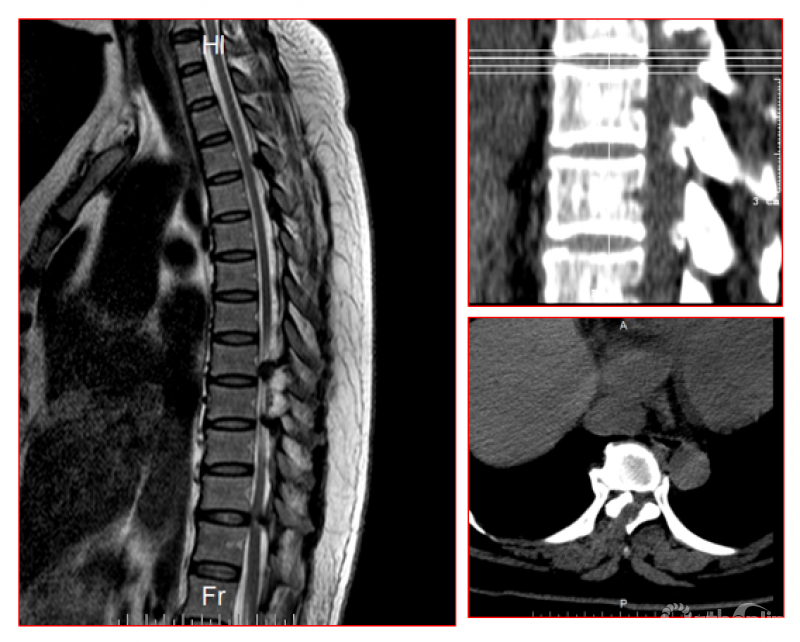

1. CT分型:按照轴位CT分为外侧型、延展型、肥厚型、融合型、结节型。

2. MRI分型:按照矢状位MRI分为圆弧形、鸟嘴型。

A.B.圆弧形(Round type);C.D.鸟嘴型(Beak type)